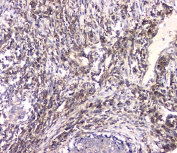

IHC staining of FFPE human lung tissue with HECTD3 antibody at 1ug/ml. HIER: boil tissue sections in pH6, 10mM citrate buffer, for 10-20 min and allow to cool before testing.